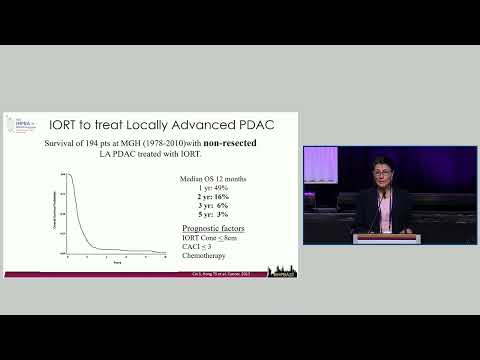

DEB13: Preferred Local Regional Therapy for Margin Sterilization Intraoperative Radiotherapy vs IRE

Debate 13: Preferred Local Regional Therapy for Margin Sterilization Intraoperative Radiotherapy vs IRE